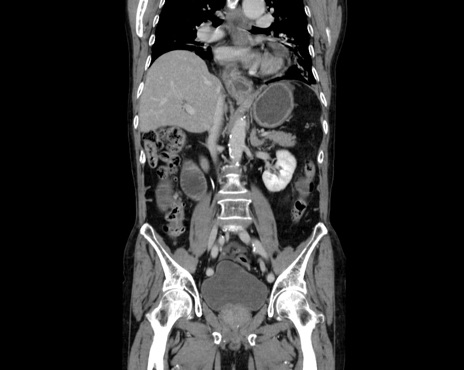

症例26(冠状断像)

【症例】80歳代男性

【主訴】嘔吐

【現病歴】昨晩2回嘔吐あり、今朝になっても嘔吐あり。来院。

【既往歴】胃潰瘍

【身体所見】意識清明、BT 37.6℃、BP 166/95mmHg、HR 100bpm、SpO2 97%、腹部:平坦・軟、腸蠕動音聴取良好、圧痛なし。

【データ】WBC 21900、CRP 1.4